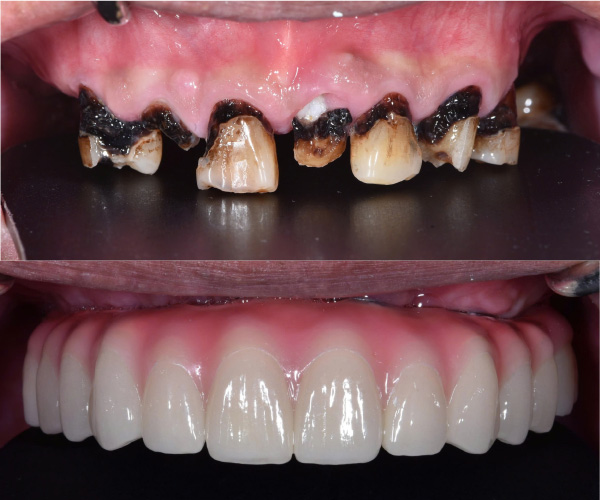

Cấy ghép implant phục hồi toàn diện chức năng nhai và thẩm mỹ cho người bị nha chu nghiêm trọng, người mất răng toàn bộ và người cao tuổi nhiều bệnh nền.

Tiến sĩ, Bác sĩ Võ Văn Nhân với hơn 23 năm kinh nghiệm trong lĩnh vực Implant Nha khoa, đã thực hiện thành công hơn 20.000 ca cấy ghép răng Implant từ đơn giản đến phức tạp. Những thành tựu đặc biệt mà Ts.Bs Võ Văn Nhân đạt được góp phần mang lại nụ cười hạnh phúc, mở ra cơ hội cho rất nhiều trường hợp mất răng, không răng bẩm sinh.